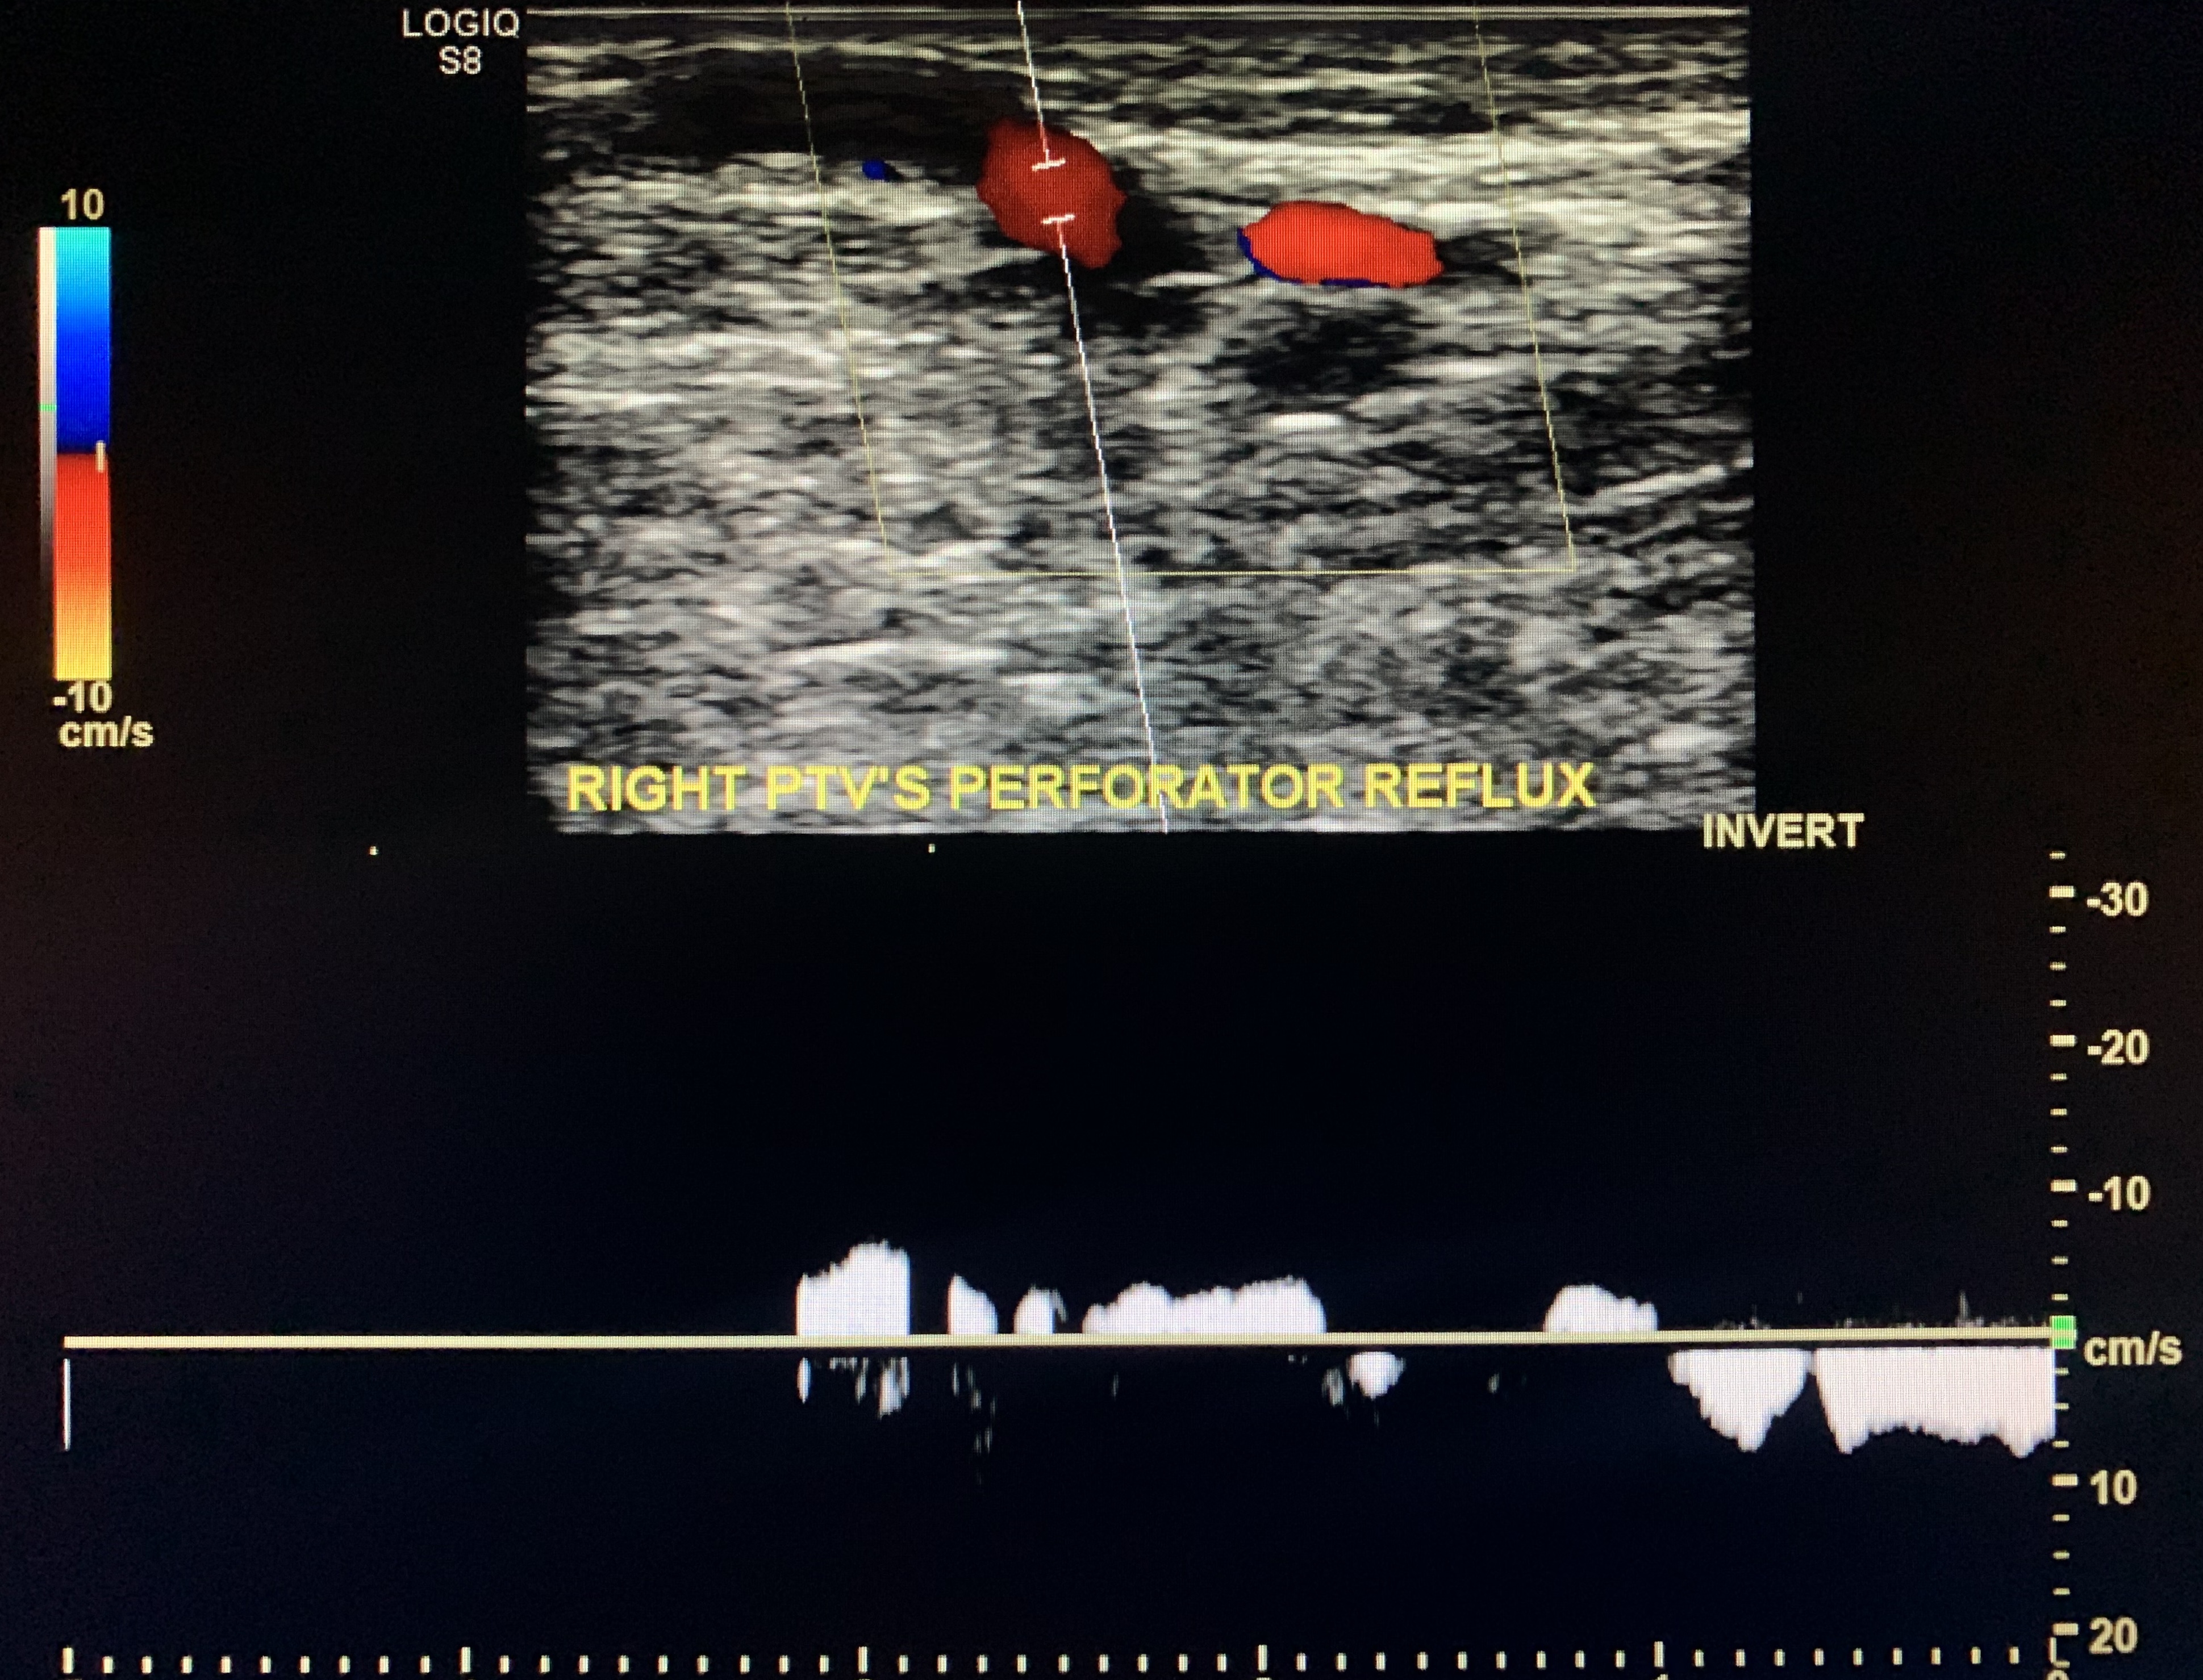

Reflux in the deep veins is considered spectral reversal >1 second. Venous reflux (Valvular incompetence) was then demonstrated in the CFV, the femoral vein, and

posterior tibial veins along with an incompetent perforator vein in the right leg.

Measure the wall diameter (varicose >3mm) of the incompetent perforator vein.

Tibial vein perforator

You can elicit retrograde flow in the incompentent vein by distal augmentation and/or asking the

patient to perform the valsalva technique (this works best from the going to mid to distal thigh

only).